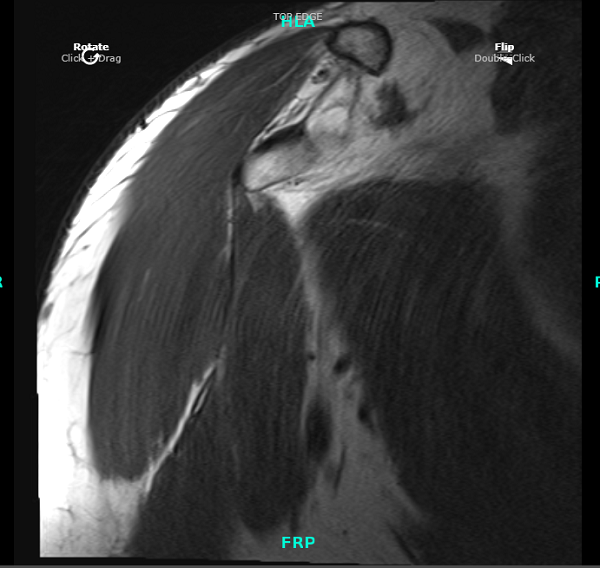

Eight weeks post operative. Patient started his PT and was doing well. We decided to have an MRI to see his shoulder condition. The MRI impression showed biceps tenodesis with surgical anchor/ endo button at the level of proximal humerus.

There is scar remodeling and heterogeneity of the tacked biceps tendon at the anchor, likely reflecting postsurgical changes. No high-grade or retracted fibers visualized.